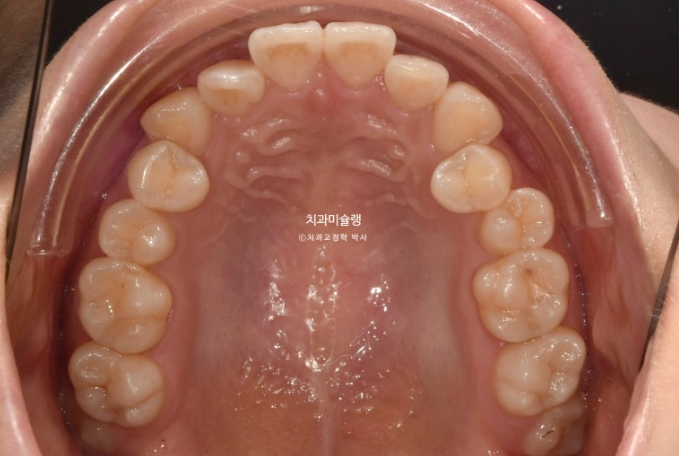

사랑니 공간을 이용하여 어금니를 뒤로 밀기 위한 교정용 나사를 입천장에 심고 진행했습니다.

어금니 교합은 물샐틈 없는 1급 교합관계 입니다.

치근흡수도 없고 치근평행도도 좋습니다.